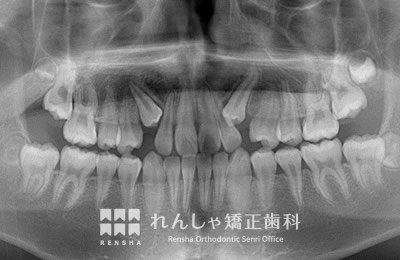

中高生

永久歯列はほぼ完成してしますが、歯列を側方だけでなく後方へも拡大し、埋まっていた右上奥歯を引っ張り出しています。

| 主訴 | 埋まったままでてこない歯がある |

|---|---|

| 診断名 | Angle Class II 小臼歯の埋伏と叢生を伴う上顎前突 |

| 初診時年齢 | 13歳5か月 |

| 装置名 | マルチブラケット装置 |

| 抜歯非抜歯 | 非抜歯 |

| 治療期間 | 2年3か月 |

| 費用の目安 | 約82万円+消費税(検査料金、都度の処置費用等も合わせた総額) |

| リスク副作用 | 歯の移動に伴う軽微な歯根吸収、歯槽骨吸収、歯肉退縮(本症例では軽度の歯根吸収を認めた)、矯正器具装着中のカリエスリスク増大(本症例ではカリエス発生無し) |